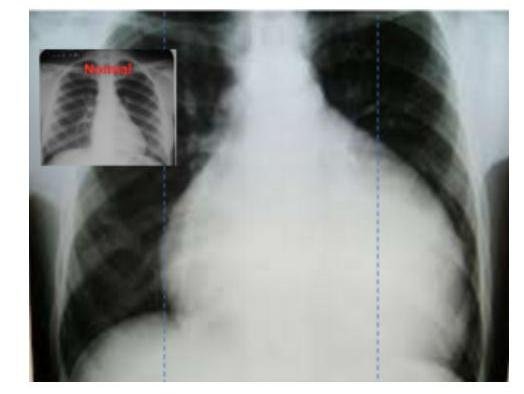

# ENFERMEDAD DE CHAGAS ## DEFINICIÓN También llamada **Tripanosomiasis americana**, es una enfermedad parasitaria exclusiva del Continente Americano cuyo agente etiológico es el protozoario flagelado **Trypanosoma cruzi** (T. cruzi), el cual es transmitido de forma horizontal entre una persona enferma y una sana, por medio del contacto con materia fecal infectada de chinches **redúvidos triatominos** (**chinche besucona**).  ## ETIOLOGÍA El parásito **Trypanosoma cruzi** tiene su **reservorio natural** en los armadillos, marsupiales, roedores, murciélagos y primates silvestres, además de perros, gatos, ratas y caballos.  ## INCUBACIÓN: 1 semana Diversas especies del género en México: Triatoma sp., T. dimidiata, T. longipennis, T. pallidipennis, T. barberi, además de Rhodnius prolixus. ## EPIDEMIOLOGÍA - Prevalencia elevada en regiones rurales más pobres de América Latina. - En México, el área de mayor prevalencia es el bello estado de **Chiapas**. - El órgano más afectado en la infección crónica es el corazón. - Descrita por el **Dr. Carlos Chagas** de Brasil. - La principal causa de muerte es la **insuficiencia cardíaca derecha**. - La falta de tratamiento oportuno lleva a la **cronicidad**. ## FACTORES DE RIESGO  CARLOS CHAGAS - **Zonas endémicas**: zonas rurales y pobres de México, Centroamérica y Sudamérica. - **Transfusión sanguínea** de paciente con la enfermedad # CLÍNICA ## CUADRO AGUDO - **Chagoma**: área dura de eritema, edema y linfadenopatía local por laceración en la piel en donde ocurrió la inoculación del parásito.  ## Chagoma de Inoculación Trypanosoma cruzi  - **Fiebre**, **anorexia**, **edema** de cara y de extremidades inferiores. - **Hepatoesplenomegalia** - **Meningoencefalitis** (en menores de 2 años). ## CUADRO CRÓNICO Se presenta después de **al menos 10 años** del **cuadro agudo**. ## CORAZÓN (principal lugar de afectación) - Alteraciones en el timo - **Miocardiopatía** segmentaria o dilatada - **Bloqueo de rama derecha** del haz de His - **Cardiomegalia** (con atrofia apical) - **Insuficiencia cardíaca derecha** - principal causa de muerte. ## GASTROINTESTINAL - **Disfagia**, **odinofagia**, dolor torácico, regurgitación - **Dolor abdominal** - **Estreñimiento crónico** - **Megasíndromes**: - **Megacolon** - **Megaesófago** ## GASTROINTESTINAL TRACT SYMPTOMS MEGAESOPHAGUS MEGACOLON # DIAGNÓSTICO ## GOLD STANDARD: RADIOINMUNOPRECIPITACIÓN - Detecta los **anticuerpos IgG** específicos que se adhieren a los antígenos de T. cruzi. - Tiene utilidad para diagnosticar la **enfermedad crónica**. ## DETECCIÓN DEL PARÁSITO En una muestra de **sangre periférica** se evidencia el microorganismo con **tinción de Giemsa**. ## RADIOGRAFÍAS - Abdominal: **Megacolon** - Torácica: **Cardiomegalia** - Cervical: **Megaesófago** ## TRATAMIENTO ## NIFURTIMOX - Adultos 8-10 mg/kg - Adolescentes 12.5 - 15 mg / kg - Niños: 15-20 mg/kg  ## BENIDAZOL - Adultos 5 mg / Kg - Niños: 5 - 10 mg / Kg ## Duración: **60 días**. Se da en mayor dosis en los niños porque son los que mejor toleran sus efectos adversos: - **Anorexia** y pérdida de peso. - **Polineuropatía**. - **Náuseas**. - **Vómito**. - **Dolor de cabeza**. - **Mareo** o **vértigo**.